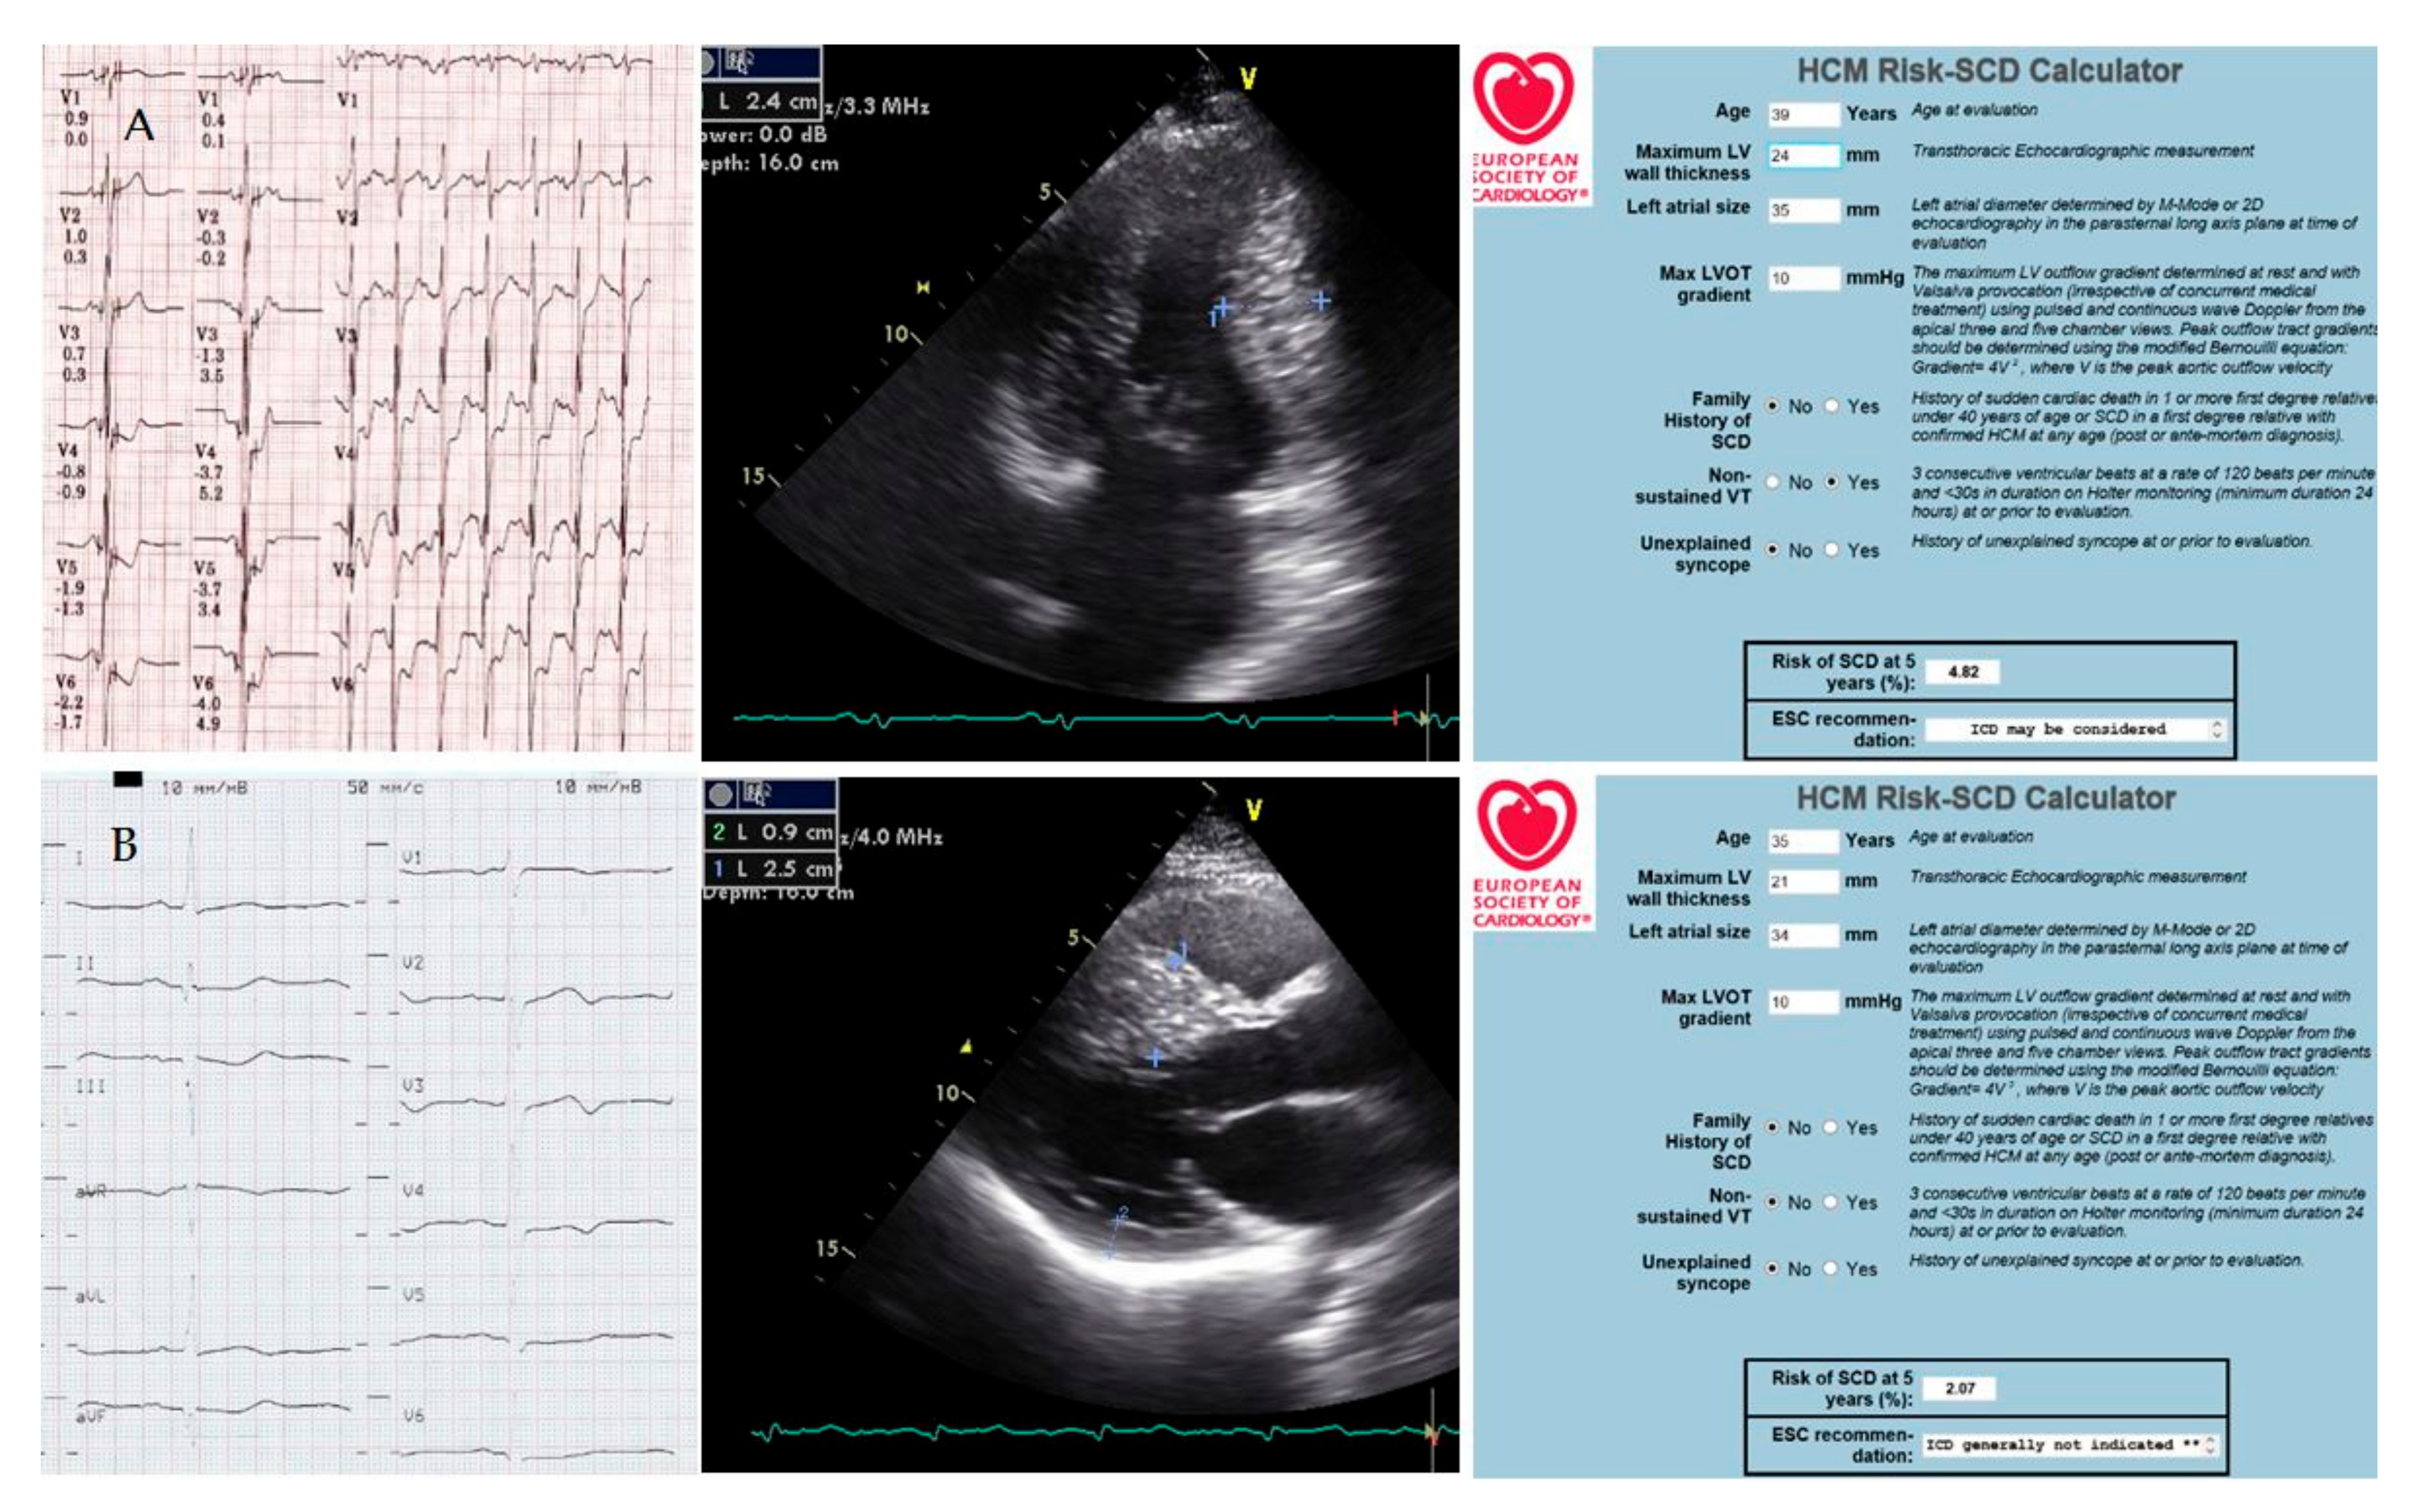

3.2. Instrumental Tests